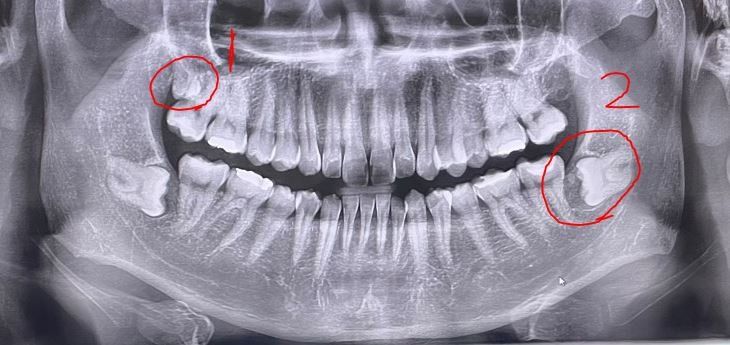

금일 사랑니 발치를 하러갔다가 2번 동그라미의 왼쪽사랑니가 함치성 낭종이라서

+1번 동그라미도 사랑니인가요?

사진으로 보이는 하악의 낭종은 경계가 명확해 보여서 악성의 가능성은 낮습니다.

낭종은 악성은 아닙니다. 다만 현재 상황으로 보아 함치성낭으로 보여지기는 하나 정확한 진단을 위해서는 반드시 조직검사를 해보아야 합니다. 다만 파노라마 사진상에서는 함치성 낭일 가능성이 큽니다. 함치성 낭에 의해 사랑니 부위 통증이 생긴다면 귀나 뒤통수까지 방사통이 나타날 수도 있습니다. 다만 신경을 따라서 뇌까지 아픈 것은 아니며 방사통 형태로 나타나는 것으로 보여집니다.

1번 부위도 사랑니입니다.

그림의 2번 왼쪽 아래 수평매복된 사랑니 주위에 작은 낭종(물혹)이 있습니다.

그림의 1번은 오른쪽 위 사랑니 입니다. 이 사랑니는 완전 매복되어 있습니다.

파노라마 영상이라 정확하지는 않으나 사진상에서 1번도 사랑니로 보입니다.